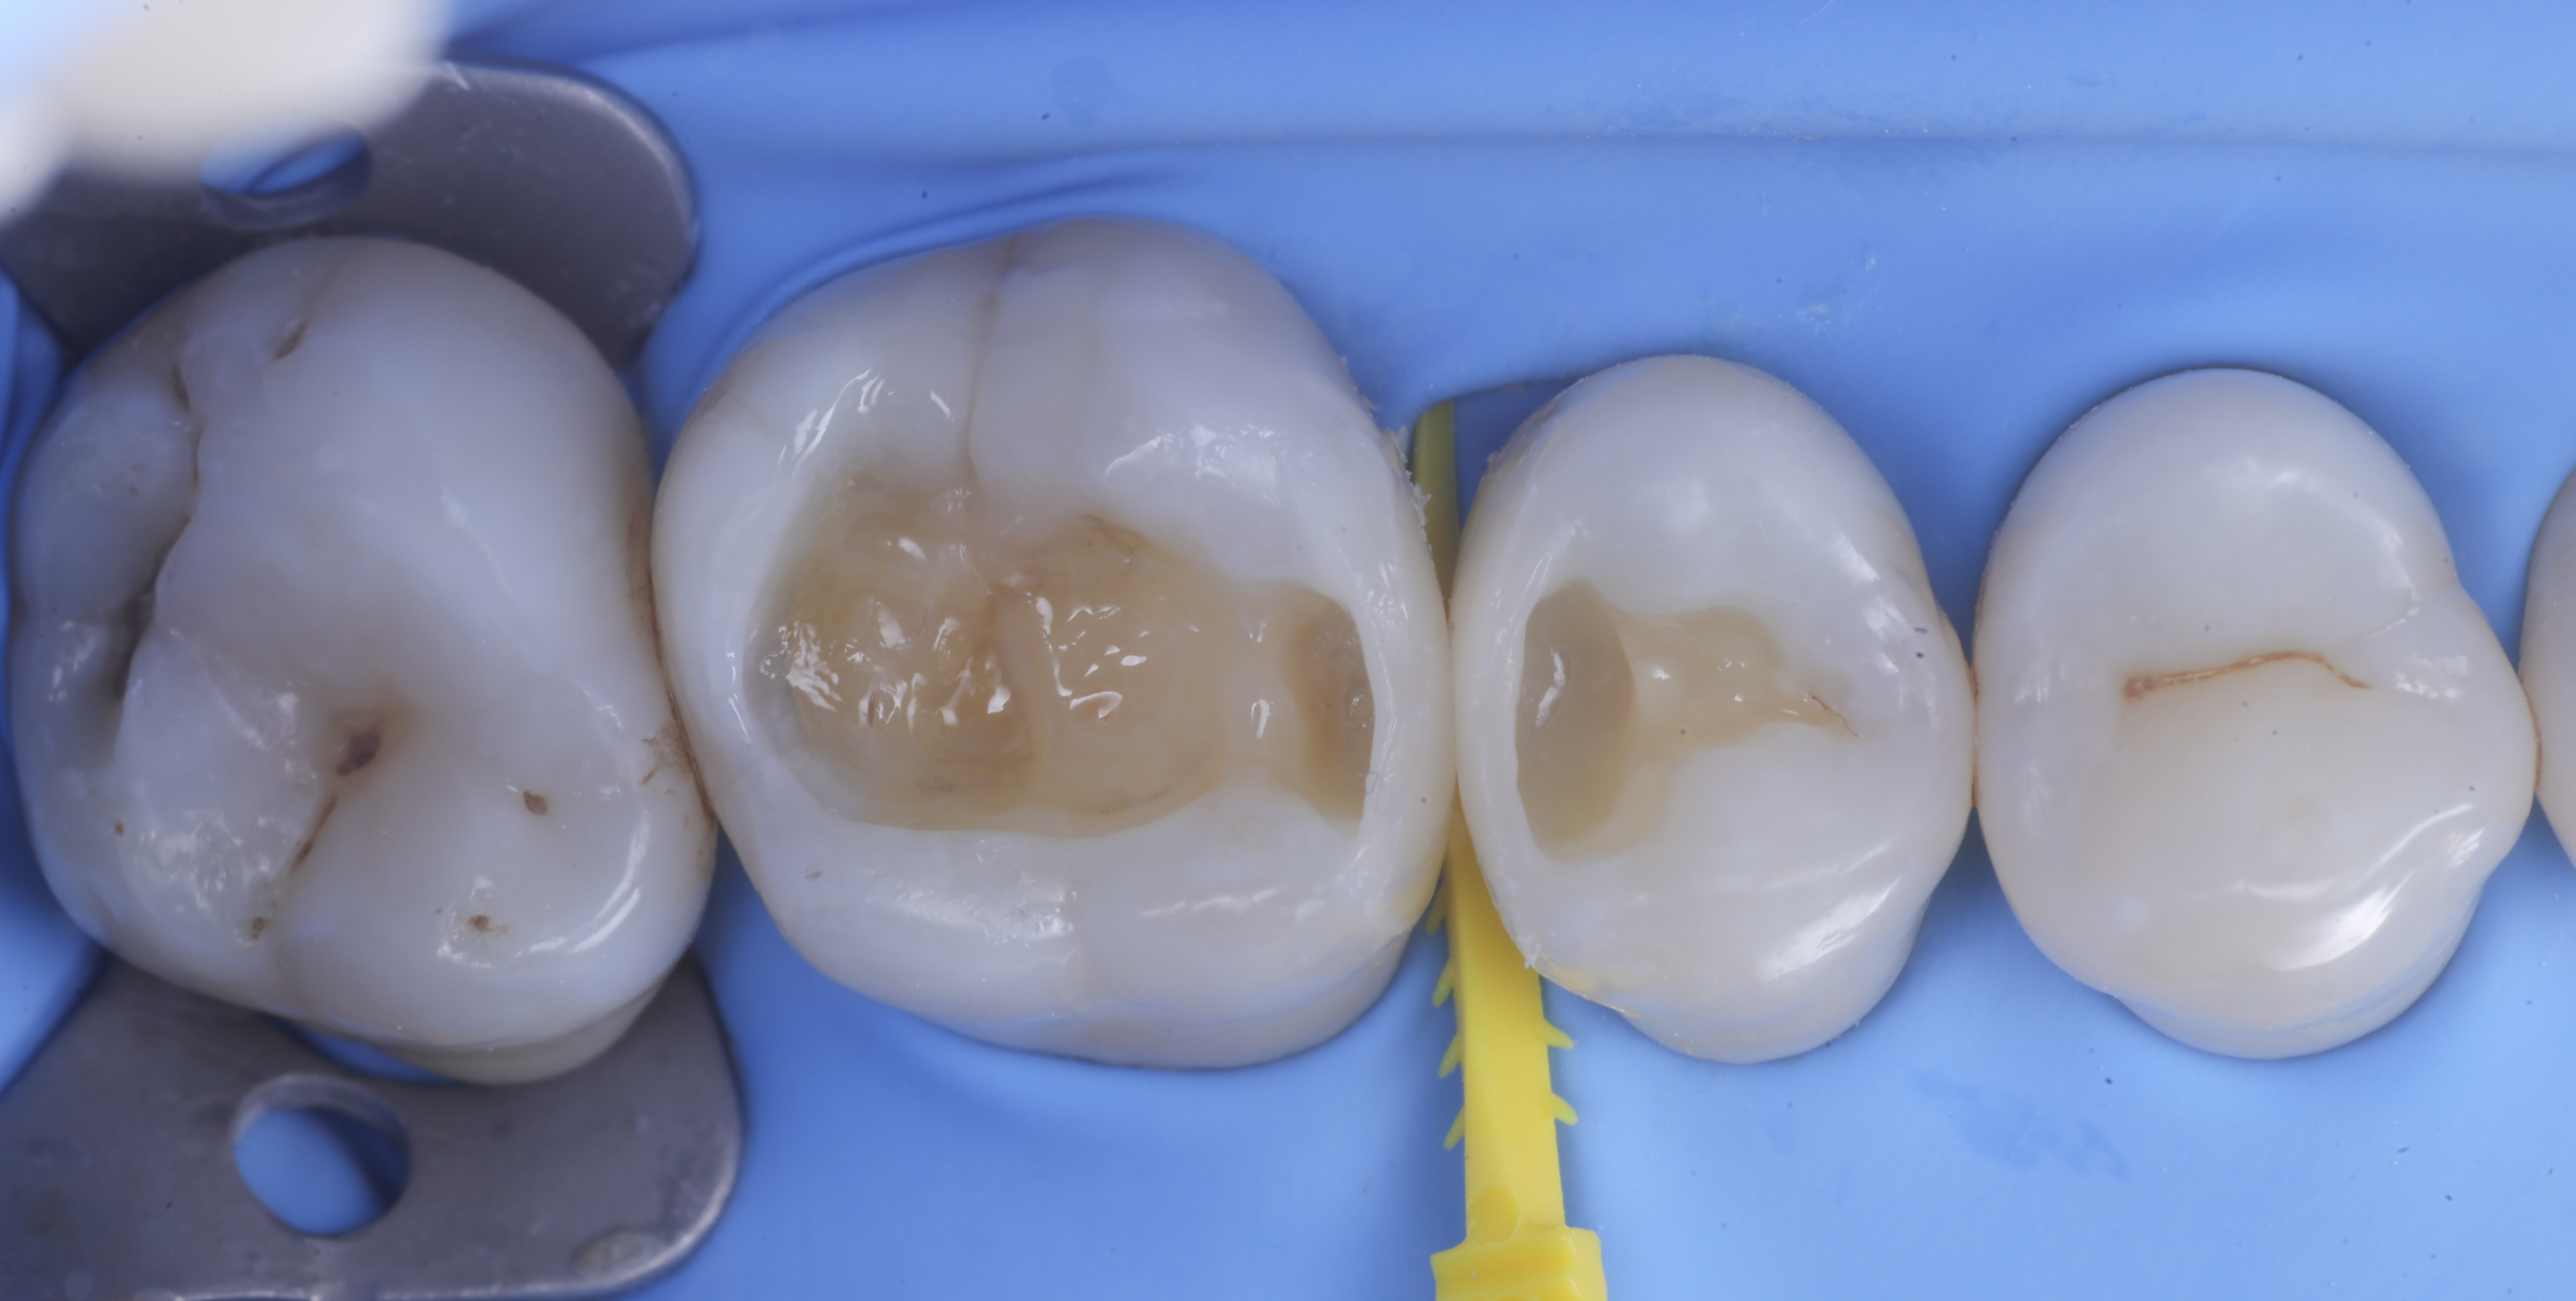

Si presenta alla nostra attenzione per dolore in zona premolare e molare del primo quadrante. Dopo un’analisi clinica e strumentale con radiografie e test diagnostici, si evidenzia la necessità di sostituire le precedenti otturazioni in composito, al fine di consegnare un migliore punto di contatto (fenomeno dell’impact food).

Come spesso accade in queste circostanze si decide per il rifacimento di tali restauri sia su 1.6 che su 1.5.

Una volta eliminato completamente il composito, si procede con la detersione della dentina con frese multilama ed alla rifinitura dei margini di smalto che dovranno essere robusti e puliti.

foto 1 Fotografia iniziale

foto 2 Isolamento e aspetto delle cavità ultimate